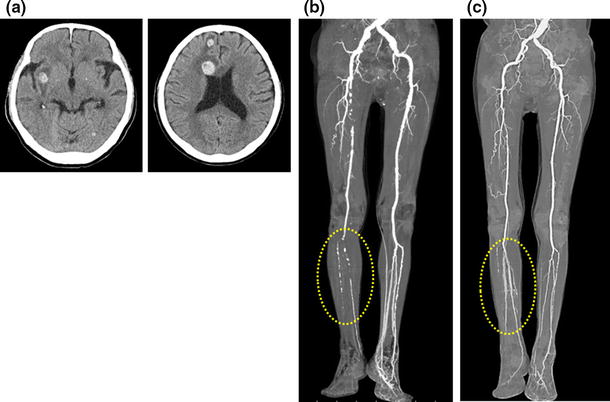

A 77-year-old male patient was referred to our hospital with frailty, accompanied with muscle weakness and gait disturbance, and bilateral lower leg resting pain. Blood tests showed severe thrombocytopenia without remarkable coagulopathy, and cranial CT revealed multiple focal hemorrhages (Fig. 1a), which suggested a potential cause for the gait disturbance. At the onset of intracranial hemorrhage, the patient’s platelet count was 0.3 × 104/μL. Diagnostic testing for thrombocytopenia was performed by examining bone marrow aspirate. We diagnosed idiopathic thrombocytopenic purpura (ITP) based on the unrepressed proliferation of megakaryocytes in the hyperplastic bone marrow (day 0). His presentation was not consistent with any other possible differential diagnosis. We did not observe any immunological abnormalities in the blood tests, including anti-cardiolipin antibody and lupus anticoagulant (anti-CL–β2GP1 complex). Soon after the diagnosis of ITP, the patient was treated with prednisolone at 1.0 mg/kg/day. His platelet count immediately recovered from 0.2 × 104 to 13.8 × 104/μL 10 days after corticosteroid treatment. Seventeen days after prednisolone treatment for ITP, the pain in the patient’s right leg was exacerbated, and ischemia and cyanosis were observed (day 17). CT angiography revealed arterial sclerosis obliterans in the right leg (Fig. 1b), with a platelet count of 17.0 × 104/μL and rhabdomyolysis, showing creatinine kinase elevation to 6798 U/L (normal range 40–200 U/L). After recovery of the platelet count, he underwent catheter intervention that restored the blood flow (day 83) (Fig. 1c).

a Bilateral multifocal cerebral hematoma on plain cranial CT. b Arterial sclerotic lesion in the patient’s right leg. c Restoration of blood flow in the tibial and peroneal arteries